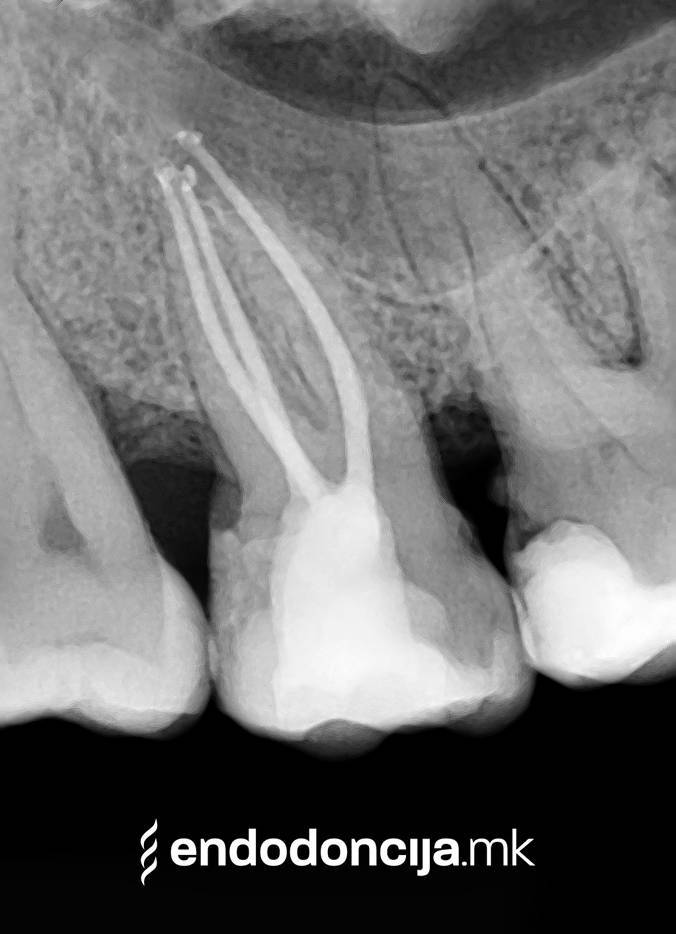

Εκτός από την ανίχνευση των ριζικών καναλιών, η ενδελεχής προετοιμασία και η απολύμανση του ριζικού σωλήνα είναι η προϋπόθεση για μια επιτυχημένη συνολική θεραπεία. Μέσω της χρήσης των νεότερων οργάνων και αντιβακτηριακών διαλυμάτων, όλα τα υπολείμματα ιστών και τα βακτήρια που υπάρχουν μπορούν να εξαλειφθούν.

Οι υπηρεσίες του Ειδικού Τμήματος Ενδοδοντικής δεν περιορίζονται καθόλου στη συμβατική επεξεργασία ριζικών καναλιών. Αντιμετωπίζουμε αποκλειστικά τους ασθενείς μας με τα νεότερα υλικά και όργανα με μικροσκόπιο, προκειμένου να είμαστε σε θέση να καθαρίσουμε εντελώς και να προετοιμάσουμε όλα τα κανάλια πριν τα γεμίσουμε.